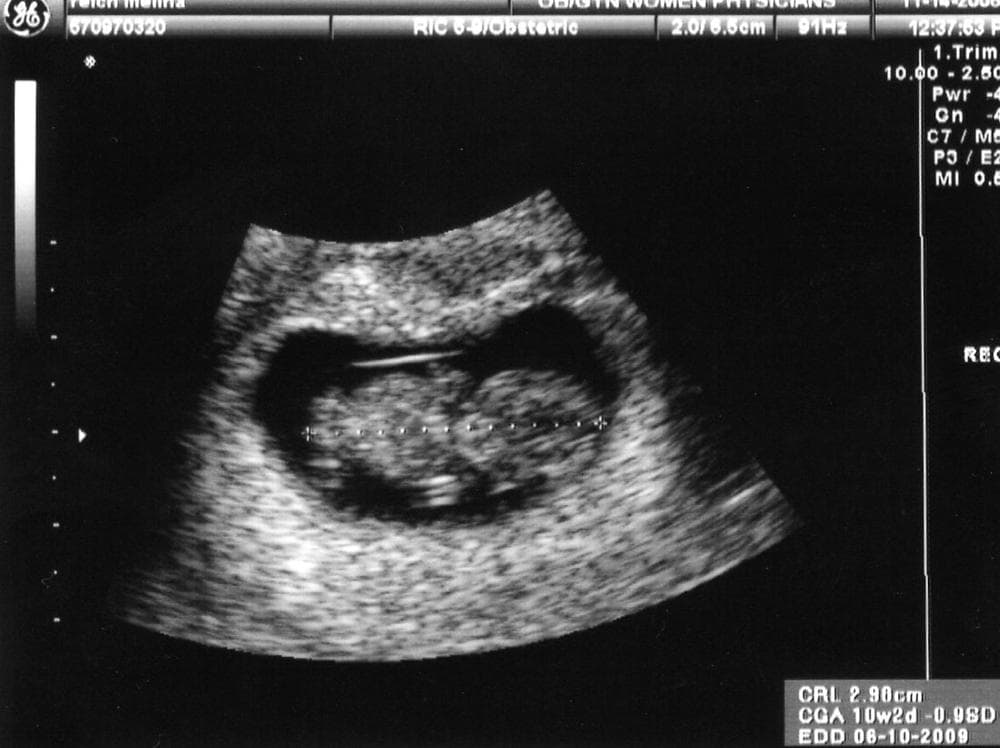

Here's a thing you've probably seen on your Facebook newsfeed at least once: A grainy, blurry, black and white picture of something that looks like a large tadpole with a backbone. And next to it, the status update, "It's a boy!" or "It's a girl!" Or maybe, with twins, "It's both!"

Point is, such fetal ultrasound images are very common. But, the whole, "it's a boy/girl" announcement doesn't usually happen until about 20 weeks into the pregnancy. That's five months, or about half way.